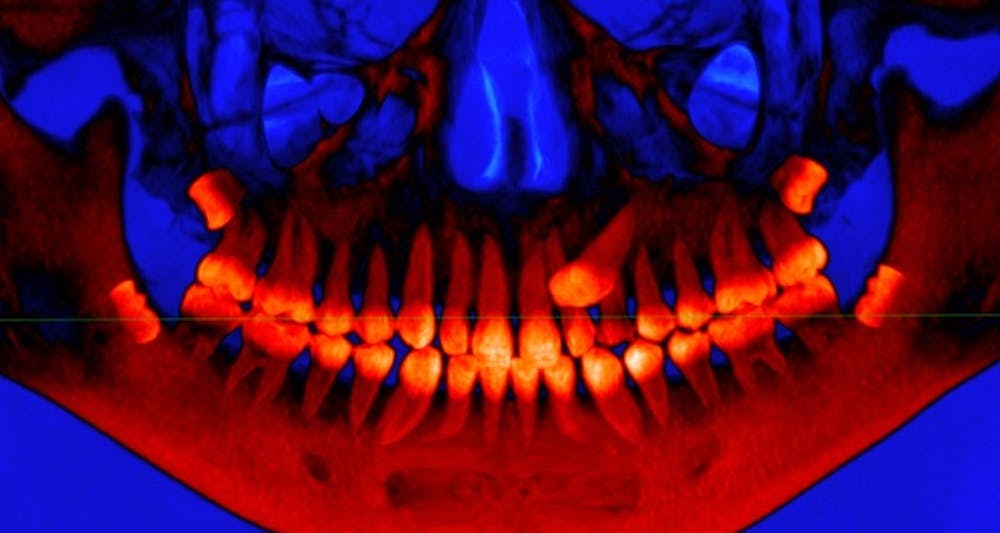

Bad Molars The Origins Of Wisdom Teeth